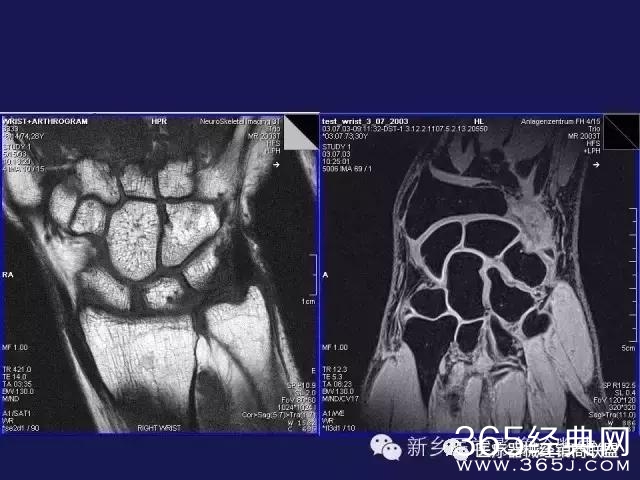

CT、MRI很难?NO,今日我们一起来学习一下如何读CT、MRI!

内行看门道:

整整90张图